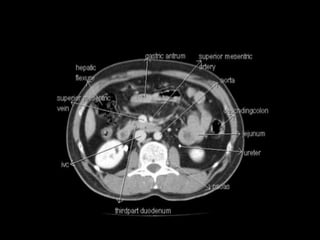

Cross section anatomy of abdominal ct scan

Cross section anatomyof abdominal ct scan